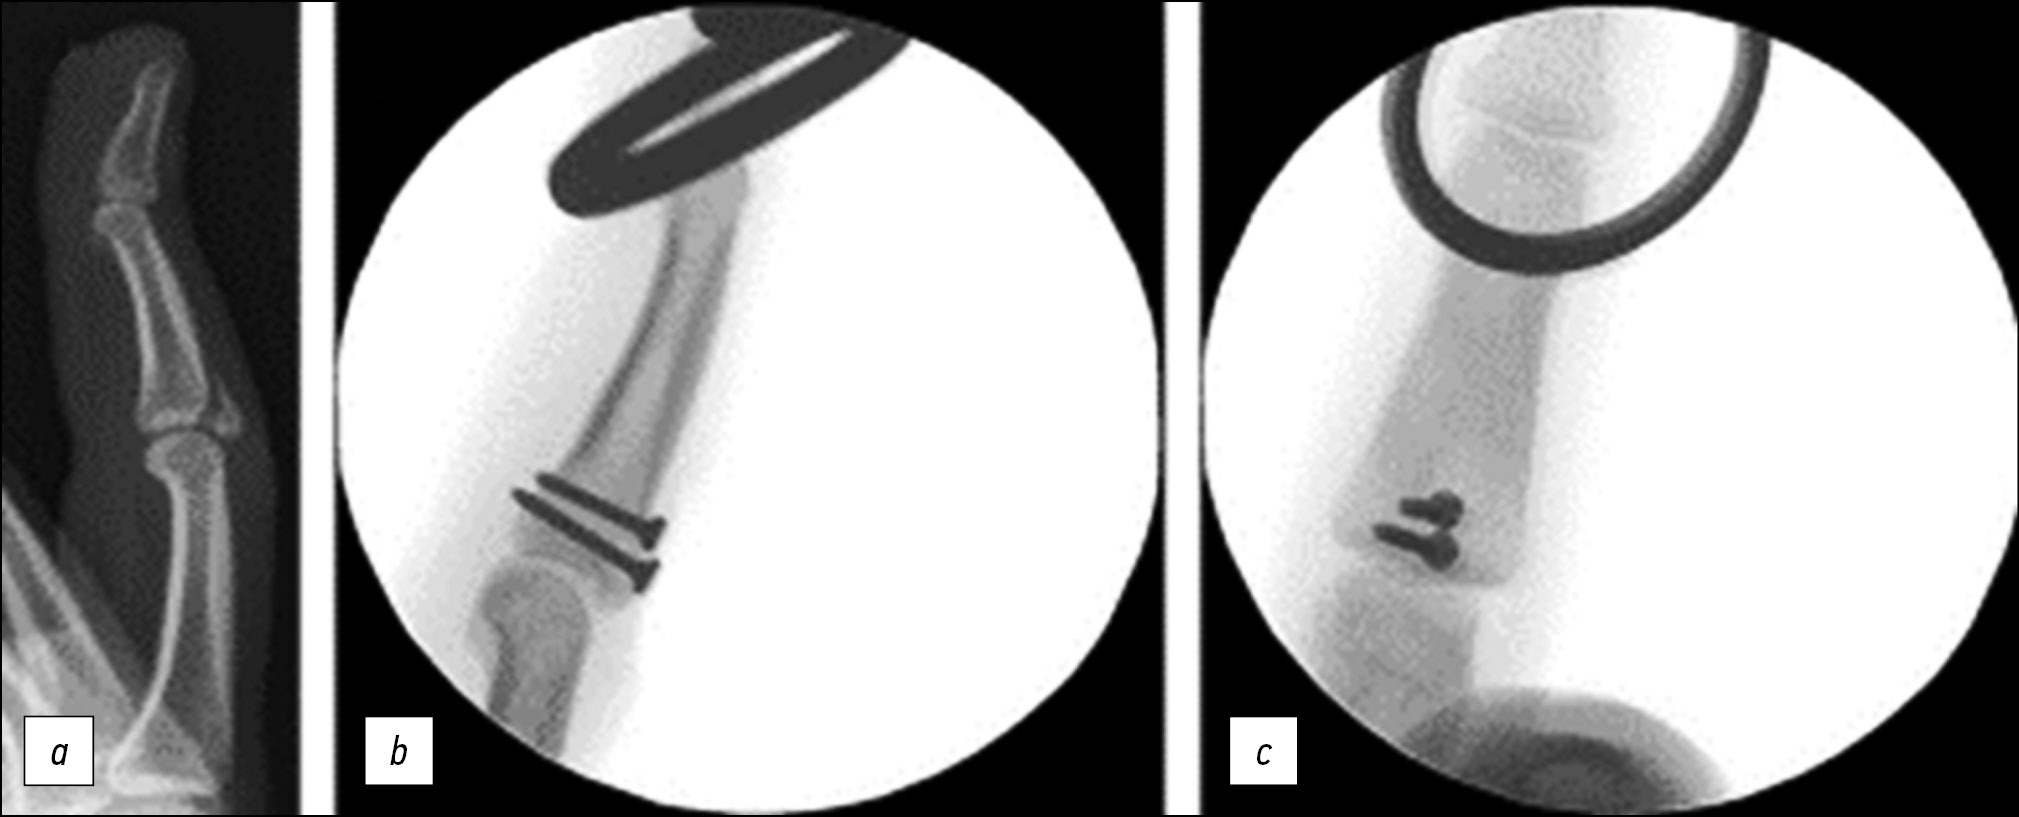

Открытая репозиция и внутренняя фиксация

Несмотря на широкую практику применения остеосинтеза винтами, уникальные анатомические особенности фаланг (скользящие структуры, тонкие кортикальные слои и небольшие костные фрагменты), остеосинтез фаланг пальцев винтами (рис. 13) является одним из наиболее технически сложных методов лечения. Однако достигнутая стабильность при данном методе лечения даёт возможность скорейшей мобилизации травмированного сегмента, что является явным преимуществом по сравнению с некоторыми другими методами. При остеосинтезе диаметр винта не должен превышать 1/3 длины линии перелома; необходимо провести минимум 2, а лучше 3 винта для создания многоплоскостной стабильности; ближний кортикальный слой дополнительно просверливается сверлом одного диаметра с наружным диаметром резьбы винта для создания скользящего отверстия и компрессии отломка [22].

Рис. 13. Остеосинтез винтами. a — внутрисуставной перелом тыльного края основания средней фаланги, b, c — остеосинтез фрагмента средней фаланги винтами [7].

Fig. 13. Osteosynthesis with screws. a — intra-articular fracture of the back edge of the base of the middle phalanx, b, c — osteosynthesis of a fragment of the middle phalanx with screws [7].

При использовании пластин (рис. 14) для остеосинтеза внутрисуставных переломов и переломовывихов фаланги в отличие от остеосинтеза винтами обеспечивается более широкая поверхность для удержания фрагментов, особенно мелких. Проксимальный край пластины может, как бы огибая по диаметру основание средней фаланги, более стабильно удерживать даже мелкие фрагменты, сохранившие связь с ладонной пластинкой [5].

Рис. 14. Остеосинтез пластиной [7].

Fig. 14. Osteosynthesis with a plate [7].